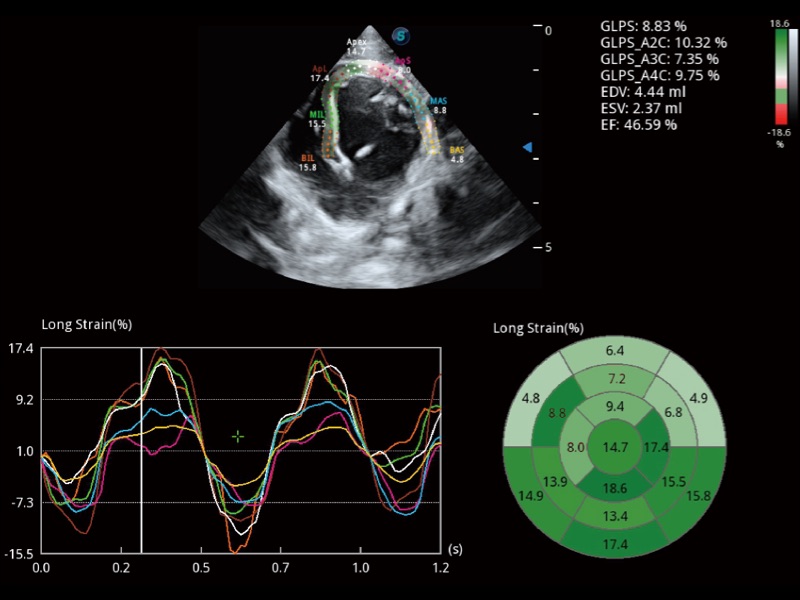

• Auto EF 心内膜自动描迹

能够基于左心室壁追踪和辛普森法,自动计算射血分数,支持多个可移动点描迹,与手动测量相比,极大节省了动物医生的时间和精力。

优异的基础图像

ProPet 70 全新的动物超声智能软件和丰富的探头群,为动物医生提供了高清晰度和精细分辨率的图像,无论在宠物、马科、畜牧还是实验室动物等应用中都可以轻松应对,为您的日常工作带来满意的体验。

(犬)四腔心MQA